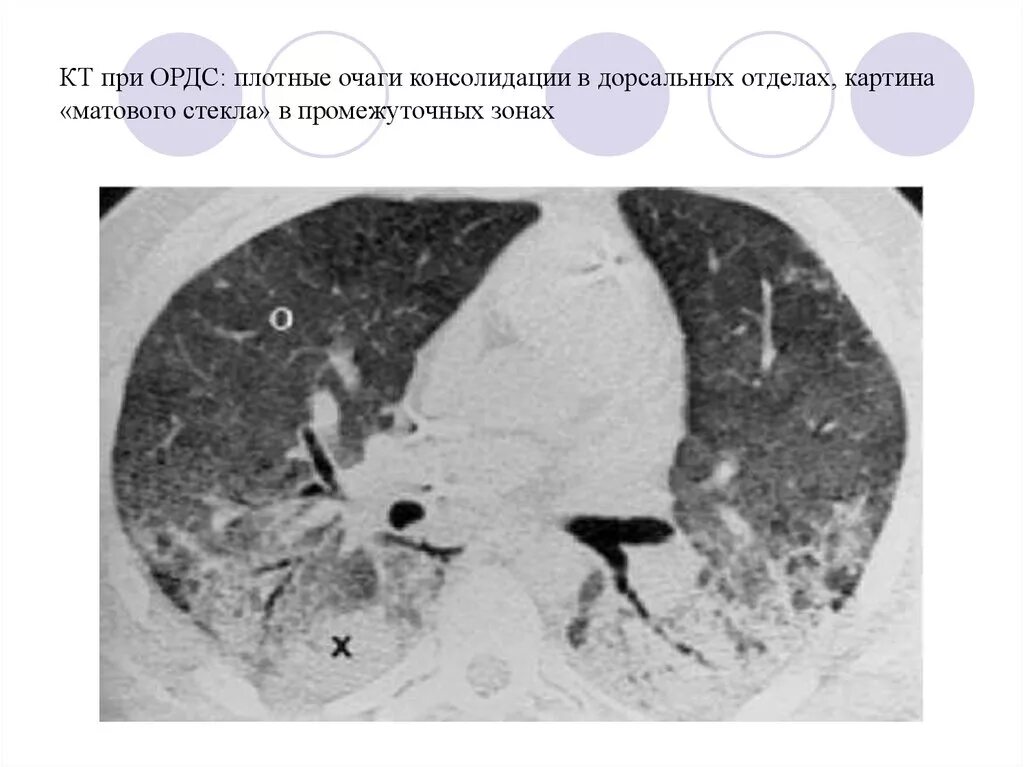

Ордс крипта